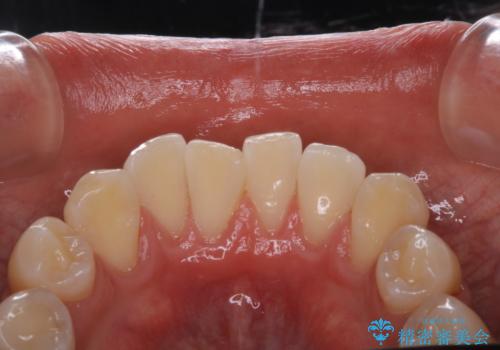

PMTCは、歯に付着した汚れを除去していくため、着色が気になる場合にも行うことができます。ご自身でのセルフケアだけで着色を落とそうとすると、逆に歯を傷つけてしまったり、精密に汚れを除去できないこともあります。また、日常生活で着色しやすい飲食物を避けたりすることはストレスに感じてしまったり、あまり現実的ではありません。

歯科医院にて、適切な処置を行うことで、長期的に安定したお口の環境が作られます。まずはカウンセリングなどもおススメです。